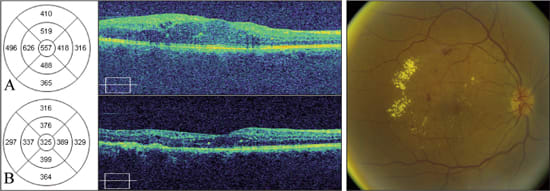

Figure 2. Sequential SD-OCT images from a 46-year-old female with diabetic macular edema in the right eye. Color fundus photograph demonstrates hard exudates with associated macular edema.

A: Horizontal scans through the fovea show distortion of the normal foveal contour with central macular thickening. The retinal map shows a central foveal thickness of 557 μm. Best-corrected visual acuity was 20/30.

B: Two months after grid laser photocoagulation, SD-OCT reveals marked improvement of foveal thickness (325 μm) and restoration of the foveal contour. Best-corrected visual acuity was 20/20.

A 46-year-old female with a history of non-insulin dependent diabetes mellitus for 19 years was referred for evaluation of diabetic macular edema in both eyes. She had no other prior medical history. Best corrected visual acuity was 20/30 in the right eye, and SD-OCT demonstrated clinically significant macular edema with a central foveal thickness of 557 microns (Figure 2A).

The patient was treated with grid laser photocoagulation in the right eye. At two months follow up, the visual acuity was 20/20. SD-OCT mirrored the clinical finding of improved macular edema, with a central foveal thickness of 325 microns (Figure 2B). At six months follow-up, visual acuity remained 20/20 with stable SD-OCT findings.